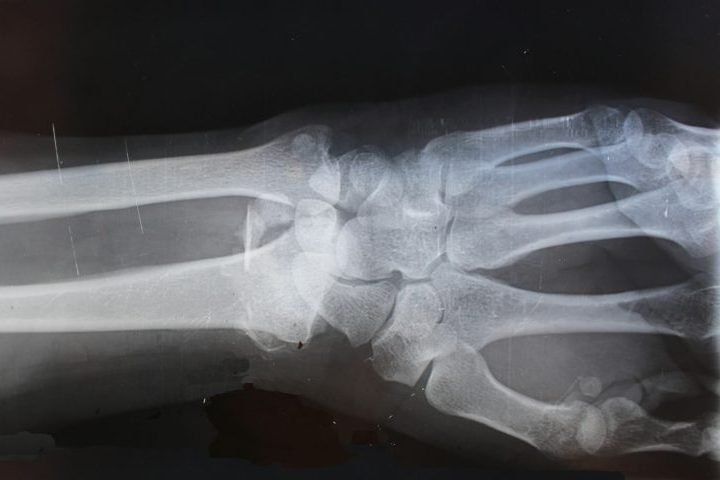

Timothy Dreyer nasceu com uma mutação genética extremamente rara – a esclerosteose – que afeta menos de 100 pessoas no mundo. Foto: Divulgação/Facebook -

"A arquitetura, a estrutura tridimensional dos ossos é normal, mas muito mais densa", explicou Alastair Henry, biólogo que estuda o caso de Tim. Foto: Freepik/DC Studio -

Segundo especialistas, os ossos dele são tão densos que são cerca de 150% mais rígidos do que granito! Foto: Wikimedia Commons/Fernando Losada Rodríguez -